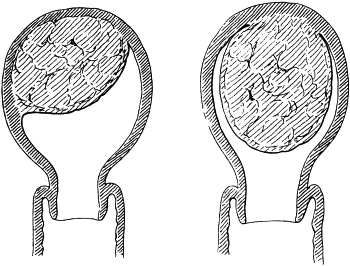

| 80. | Cystoid Scar after Glaucoma Iridectomy | 185 |